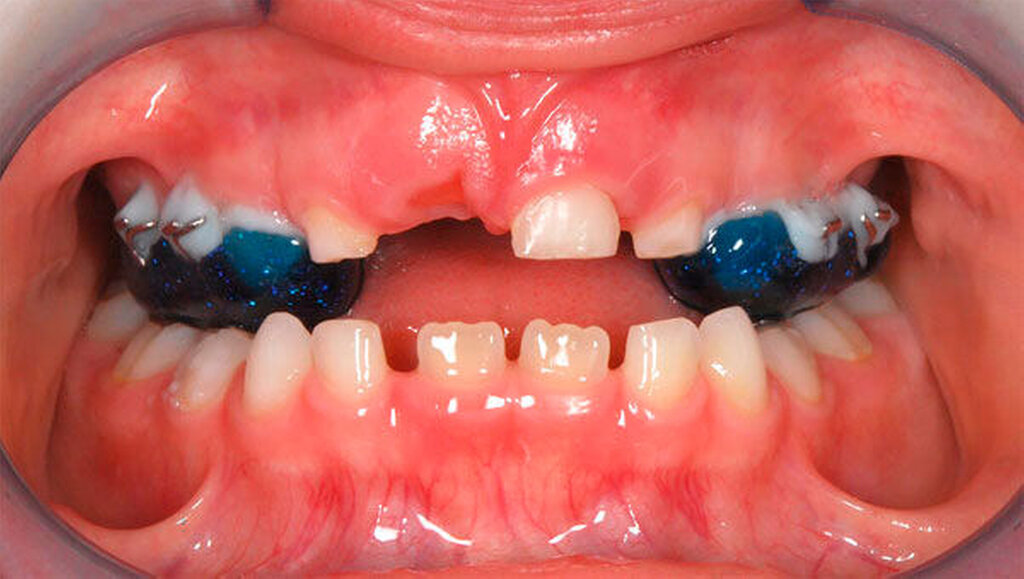

Besonders wichtig ist aus zahnärztlich-kieferorthopädischer Sicht die Beurteilung der lateralen Okklusionsverhältnisse [Kahl-Nieke, 2015]. Der unilaterale Kreuzbiss kommt ungefähr viermal häufiger vor als der bilaterale [Schopf, 2003]. Bei 80 Prozent der Kinder mit einseitigem Kreuzbiss tritt eine funktionelle Unterkieferabweichung auf [Kurol, 1992] und die Unterkiefermitte verschiebt sich dabei zur Kreuzbissseite [Santos Pinto, 2001] bei gleichzeitig asymmetrischer Kondylenposition. Diese reflektorische Einnahme der Kreuzbissstellung vergrößert die Anzahl der Okklusionskontakte, mit der Gefahr, dass nach kurzer Zeit diese transversale Fehlstellung des Unterkiefers neuromuskulär fixiert wird. Bei Belassen des Kreuzbisses kann eine skelettale Manifestation der Asymmetrie und eine dauerhafte Abweichung der Kinnmitte von der Gesichtsmitte resultieren [Hesse, 1997; O`byrn, 1995]. Erfolgt keine frühzeitige Therapie, besteht zudem die Gefahr einer Wachstumshemmung im Bereich der im Kreuzbiss „eingefangenen“ Oberkieferseite. Eine kieferorthopädische Frühbehandlung scheint präventiv gegen eine skelettale Adaptation und gegen eine Persistenz des Kreuzbisses in die permanente Dentition zu wirken [Harrison, 2001]. Das Überstellen des lateralen Kreuzbisses durch transversale Weitung des Oberkiefers kann beispielsweise mittels forcierter Gaumennahterweiterung [Köbel, 2017] erfolgen und wirkt sich neben einer Verbesserung der respiratorischen Situation günstig auf die Beseitigung skelettaler und dentoalveolärer Asymmetrien aus [Hesse, 1997; Santos Pinto, 2001] (Abbildung 3).